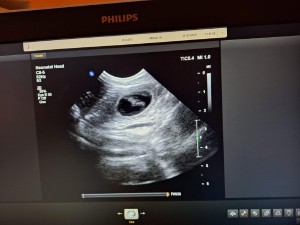

BŘEZOST POTVRZENA

Dnes jsme dostali, trošku v předstihu, nádherný vánoční dárek.

Dopoledne jsme byli s Emičkou

na sonu. Nejprve jí dělala paní doktorka sono ve stoje, ale říkala, že jsou ve stoje ta miminečka vidět hůř. Takže jsme Emičku položili, což byl jako vždy nadlidský úkon, ona je neskutečně hysterická, ale nakonec se nám to podařilo a doktorka se mohla na tu nadílku podívat. A konečný verdikt zněl 5 až 6 štěňátek. Takže přibližně v polovině ledna 2026 bude u nás veselo![]()